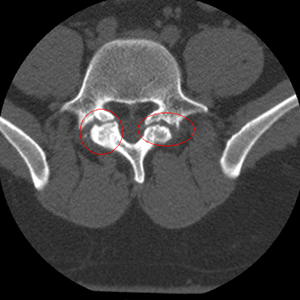

Girlchild has spondylolysis, by the way. Hardest word in the world to spell. Genetic abnormality in the vertebrae. She has two fractures that kinda look like this…

Tomorrow, they will put two small pins in across the fractures, then put bone grafts in from her ileum, plus some growth factor to promote healing. She wears a brace for 3 months and then should be able to go back to everything she was doing before…no fusion. It’s kinda scary. But she’s been in pain for almost 3 years now and they won’t heal, so it’s time to fix them. Here’s hoping she has a pain-free senior year. Here’s hoping I don’t have a panic attack in the waiting room.